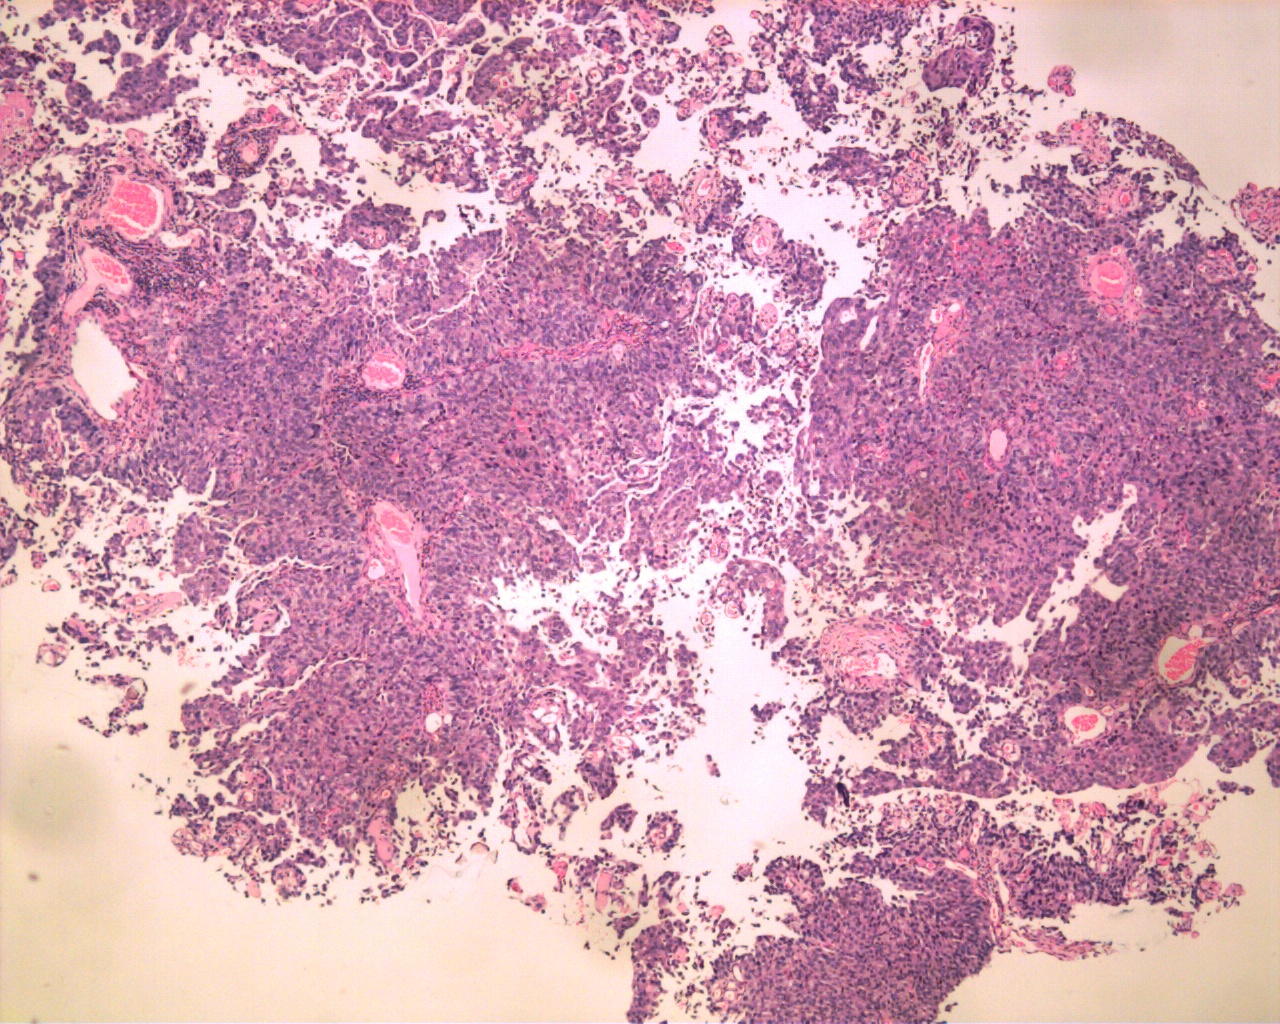

Consensus grade: High-grade papillary urothelial carcinoma (HG-PUC)

Case description (by case creator):